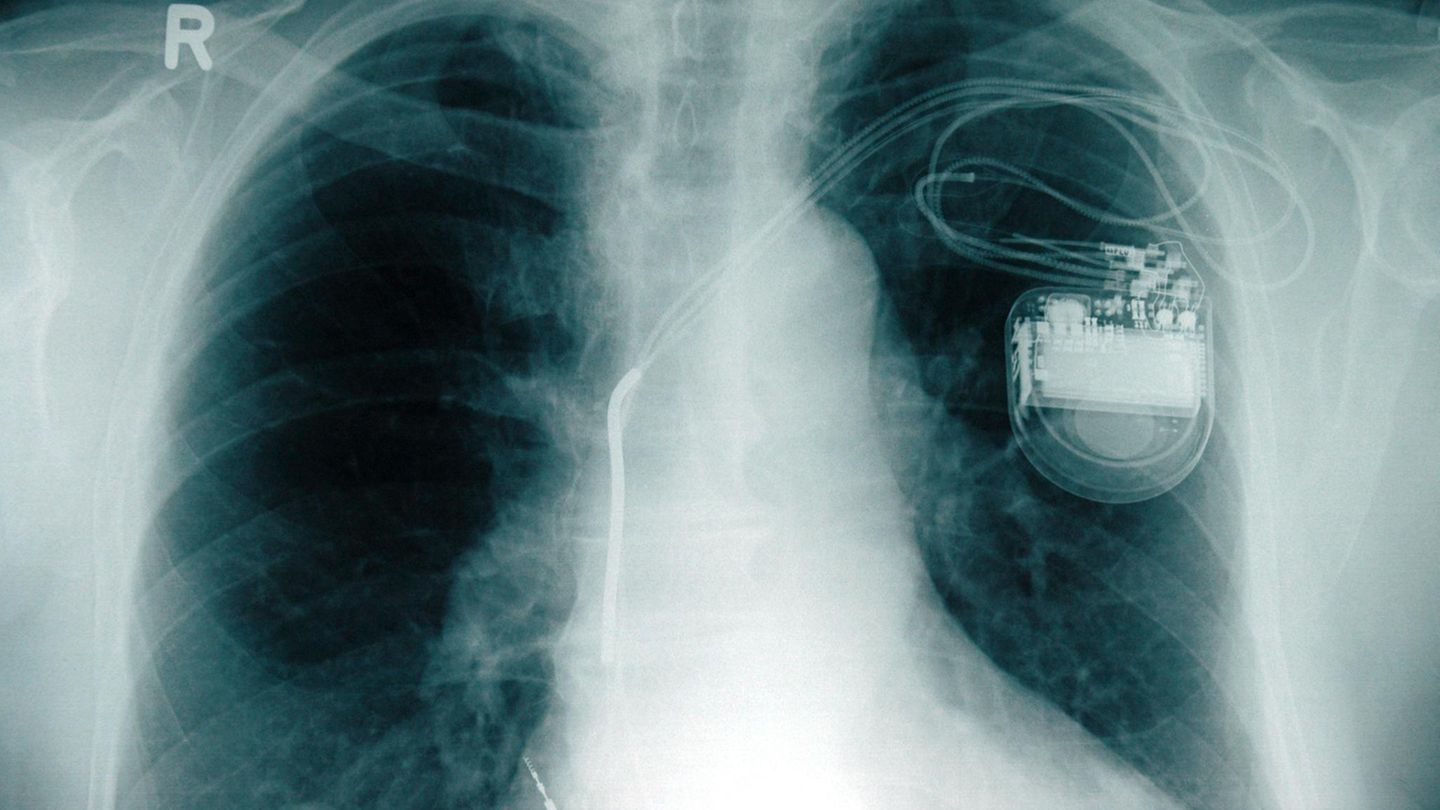

In den USA sind rund 465.000 Implantate betroffen. Ein Konzernsprecher sagte der BBC, dass weltweit 745.000 Menschen ein solches Update bräuchten. Spiegel Online berichtet, dass in Deutschland rund 13.000 Implantate betroffen seien. Das kleine Gerät verhilft Patienten mit Herzschwäche oder Rhythmusstörungen zu einem gleichmäßigen Herzschlag. Die Funktionen und die Batterielaufzeit müssen regelmäßig überprüft werden.